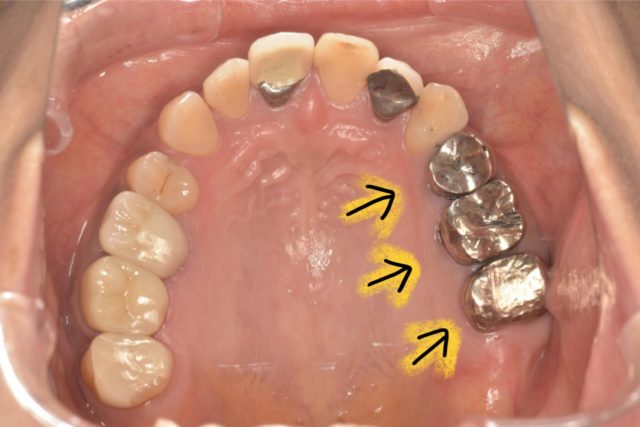

今回の患者様はフェルールが無い事から、歯冠延長術を行う事になりました。

①歯肉を下げる前の状態